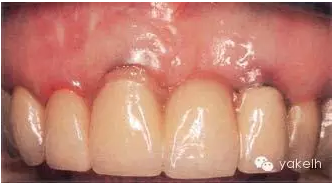

患者前牙3個(gè)單位的固定橋修復(fù),UR1和UL2為種植體(圖.7),存在美學(xué)問題。為了糾正修復(fù)位點(diǎn)的軟組織缺陷,修復(fù)體選用粉色瓷層,這樣可以調(diào)整牙齒的大小和外形。但是該病例左上兩種植體頸部金屬外露,周圍黏膜存在炎癥,同時(shí)種植體周圍軟組織下方透出灰色。

圖.7 修復(fù)體選用粉色齦層糾正了軟組織缺陷,種植體頸部暴露影響美觀效果。